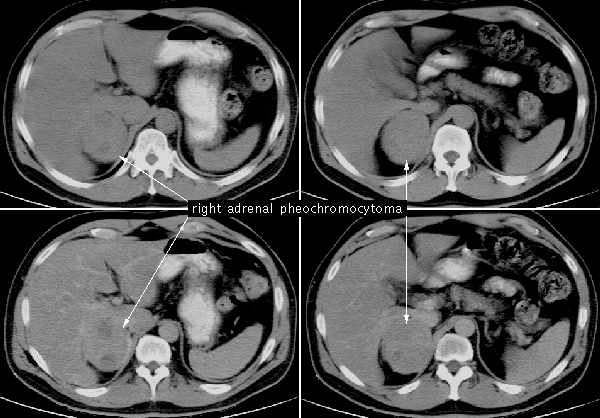

Феохромоцитома

Опухоль поражает мозговое вещество НП и продуцирует катехоламины (адреналин и норадреналин). В 90% случаев доброкачественна, но опасна тяжёлыми осложнениями. Злокачественный вид опухоли коварен своим нетипичным расположением вне железы. Доказано, что 10% случаев заболевания носят наследственный (семейный) характер. Чаще поражает женщин (30–50 лет) и впервые даёт о себе знать частыми изнурительными вегетативными кризами. Болезнь может протекать в трёх формах:

Для подтверждения диагноза, специалист-эндокринолог, помимо традиционных способов диагностики опухоли — УЗИ, КТ с болюсным контрастом и МРТ; может назначить и дополнительные: